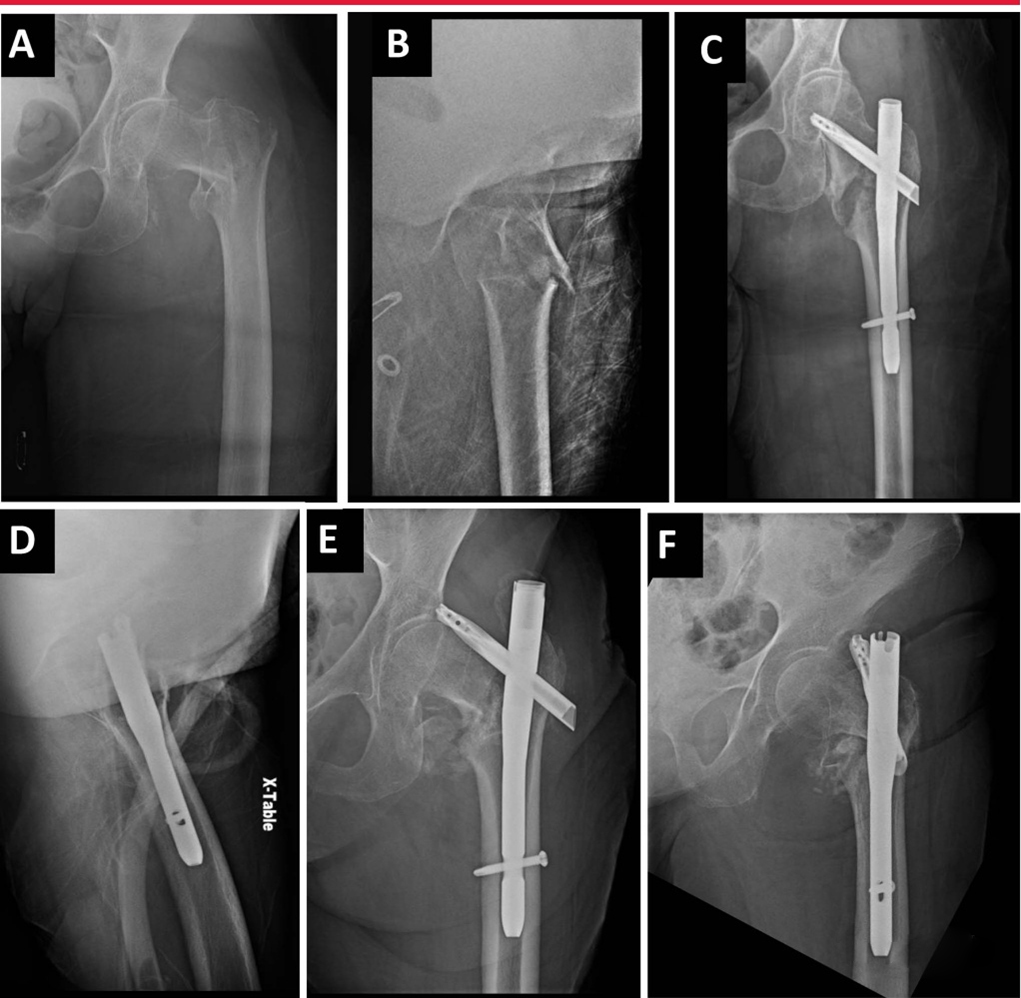

Интраоперационная боковая рентгеноскопия бедра для оценки репозиции и имплантата. А. Боковое изображение, наиболее подходящее для имплантата, демонстрирующее коллинеарность головки, шейки бедренной кости и оси бедренной кости. Б. Боковая рентгенограмма того же тазобедренного сустава во внутренней ротации. C: Повернутое наружу боковое изображение того же бедра, оптимальное для оценки переднемедиальной кортикальной поддержки и репозиции вертельных переломов. D–F: интраоперационные рентгеноскопические изображения, полученные в положении лежа на столе для переломов, показывающие вид в прямой проекции (D), боковой вид имплантата (E) и боковой репозиции (F).

Реверсивные межкарцеральные переломы представляют особые трудности при репозиции и имплантации. Необходимо проводить различие между высокоэнергетическими и низкоэнергетическими переломами вертела, поскольку эти переломы «выглядят» по-разному (изображение ниже). В то время как низкоэнергетические переломы можно успешно лечить с помощью закрытой репозиции на операционном столе, высокоэнергетические переломы часто требуют чрескожной или открытой репозиции.

Боковая рентгеноскопия левого бедра показывает значительное смещение фрагментов перелома, несмотря на адекватную тракцию и ротацию на операционном столе для переломов.